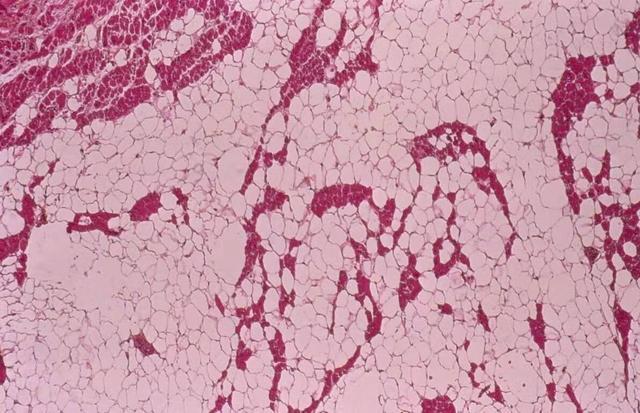

可能你不知道脂肪瘤,但是你总知道什么是脂肪吧,其实脂肪瘤就是成熟的脂肪细胞聚集形成,换句话说只要有脂肪的地方都有可能长脂肪瘤,所以手术切下来一般也都是黄色的脂肪组织团块。